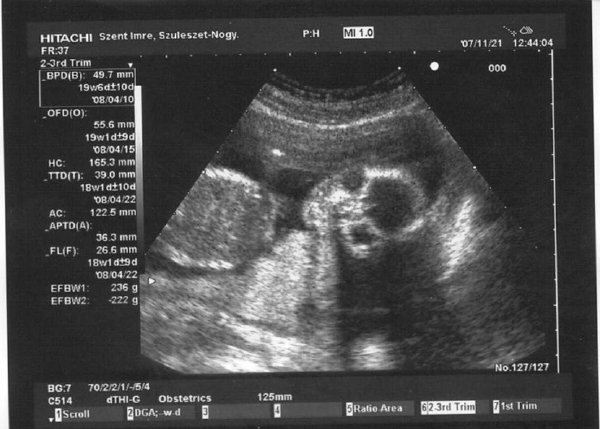

holnap meg 20 hetes genetikai uh.